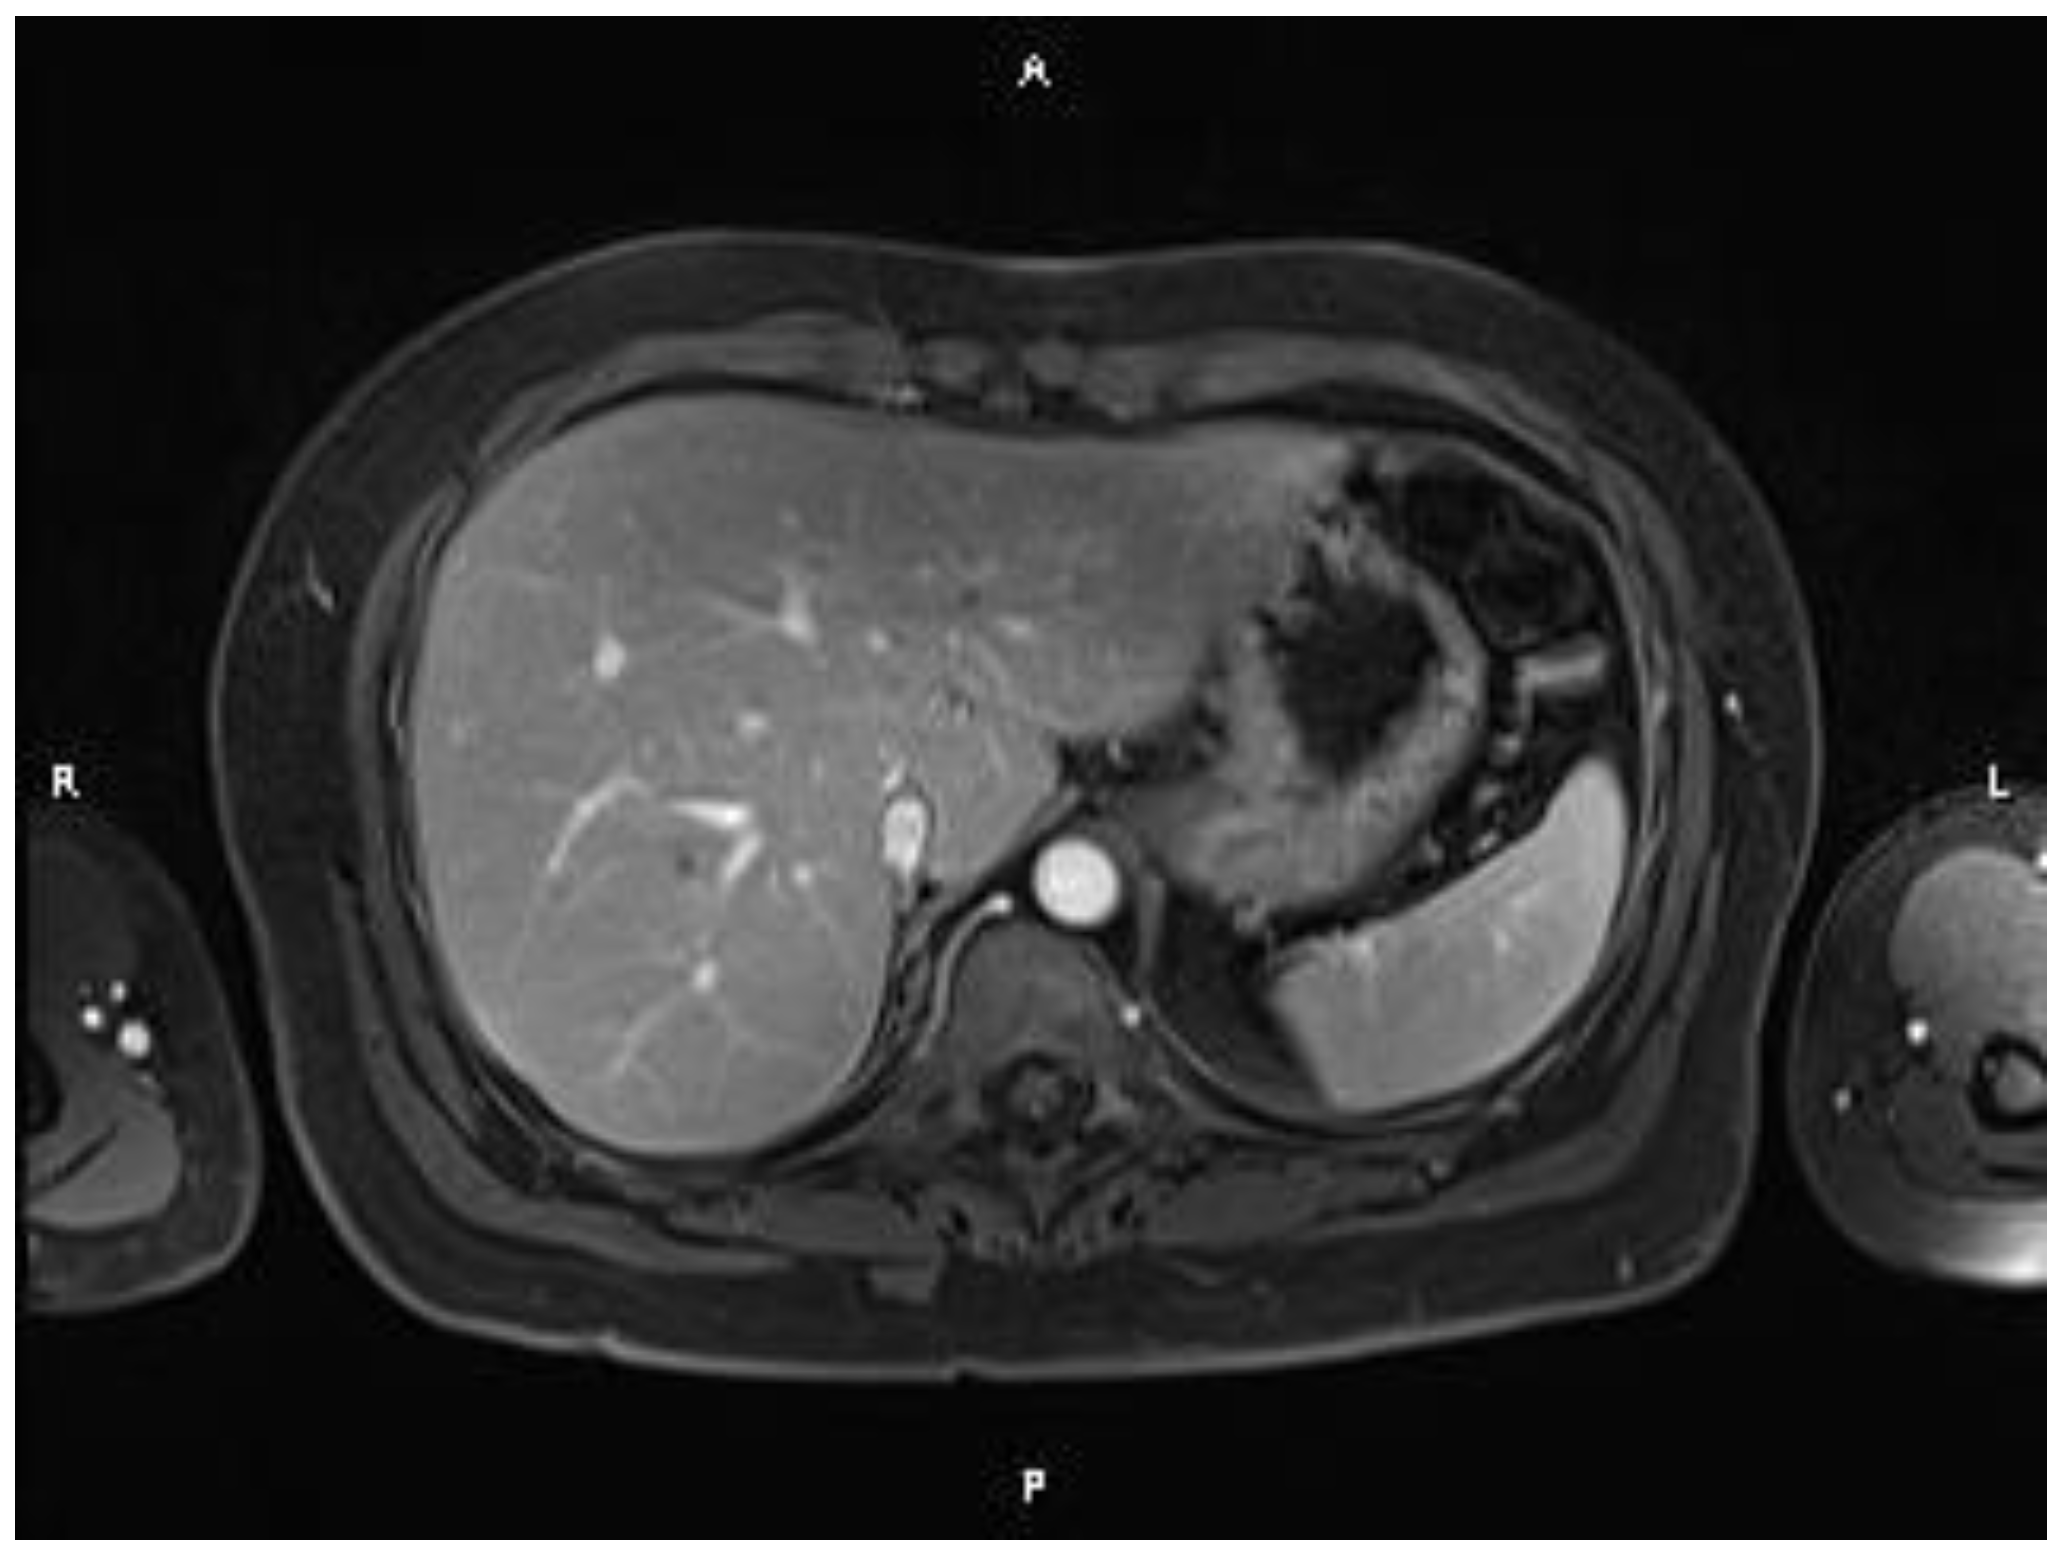

2. Case Report